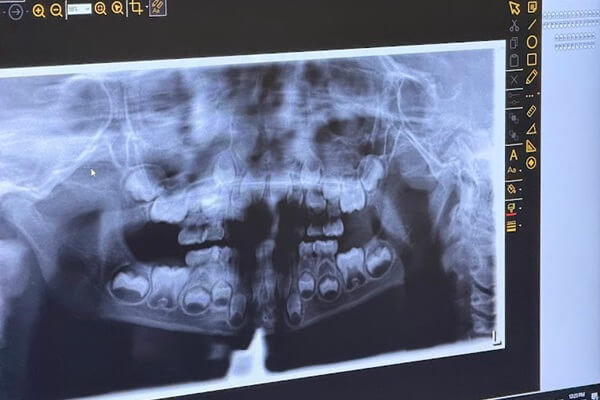

Comprehensive Oral Exam

A comprehensive oral exam is the starting point for understanding your overall oral health. This appointment is designed to create clarity, establish a baseline, and provide a calm, informative experience whether you’re new to the clinic or returning after time away.